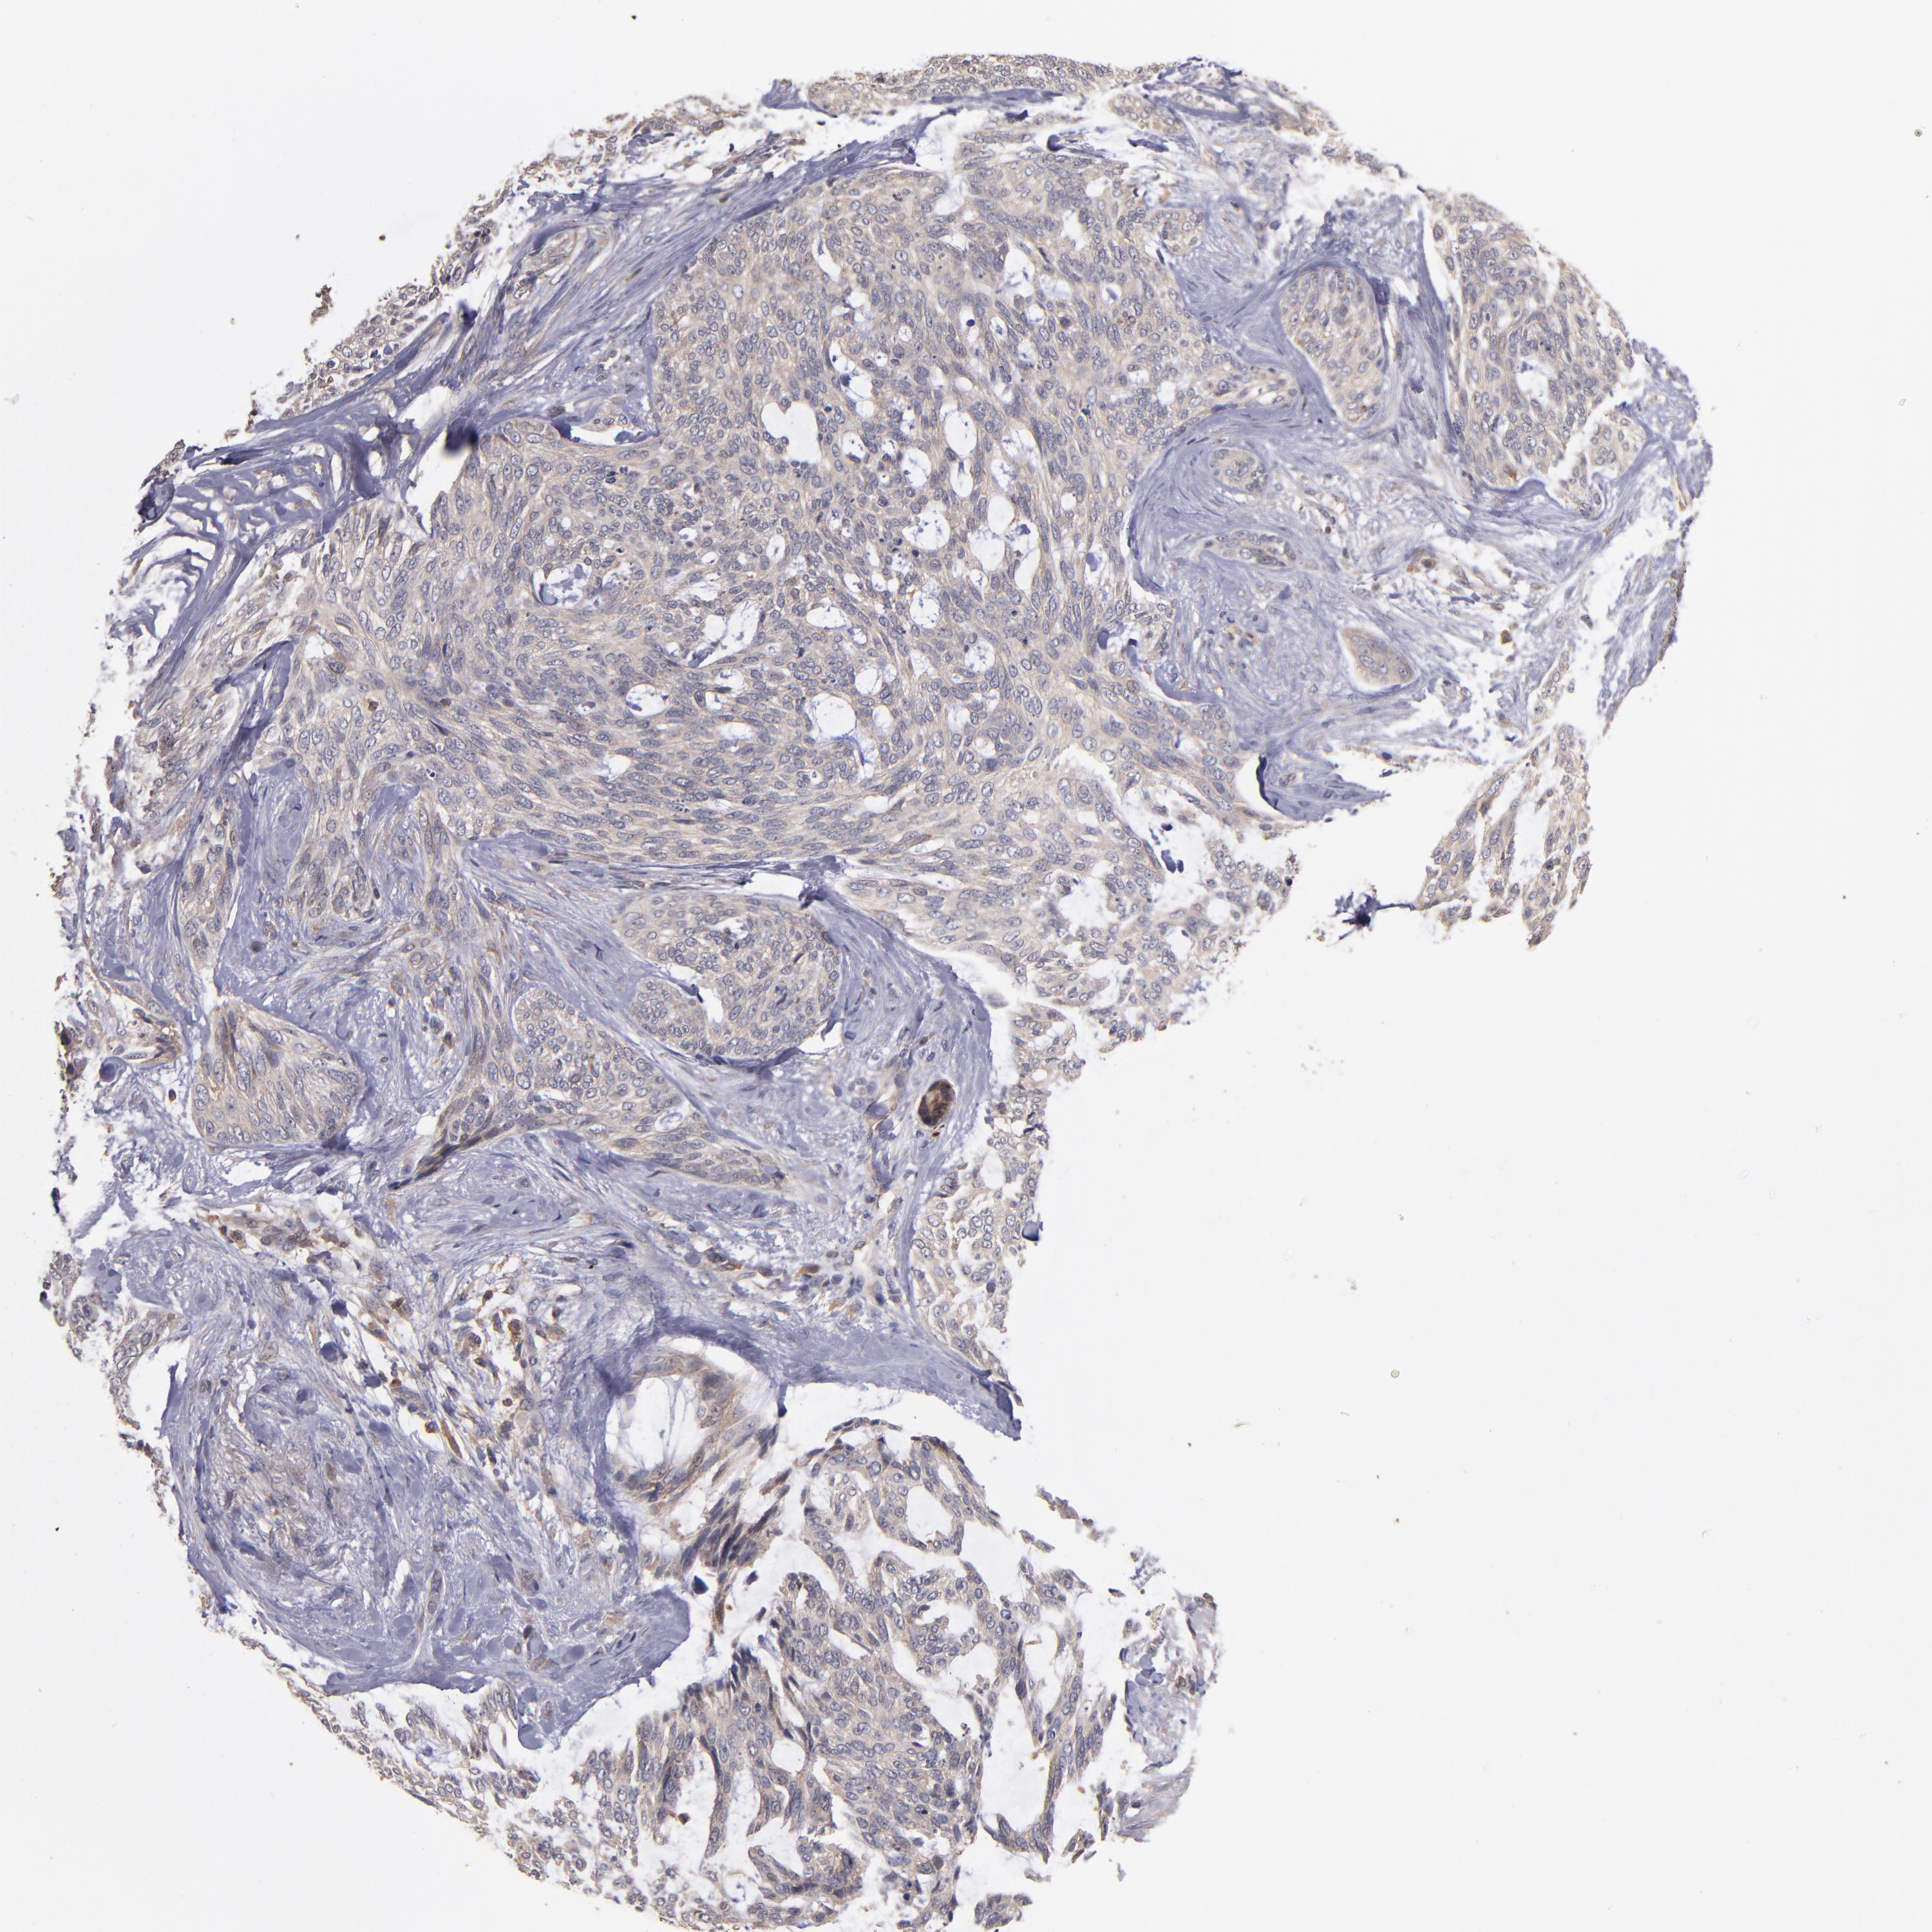

SKIN CANCER - Protein expressioni

A mouse-over function shows sample information and annotation data. Click on an image to view it in a full screen mode. Samples can be filtered based on level of antibody staining by selecting one or several of the following categories: high, medium, low and not detected. The assay and annotation is described here.

Antibody stainingi

Antibody staining in the annotated cell types in the current human tissue is reported as not detected, low, medium, or high, based on conventional immunohistochemistry profiling in selected tissues. This score is based on the combination of the staining intensity and fraction of stained cells.

Each image is clickable and will lead to virtual microscopy that enables deeper exploration of all samples and also displays staining intensity scores, fraction scores and subcellular localization as well as patient and tissue information for each sample.

Antibody CAB005385

Staining

High

Medium

Low

Not detected

Intensity

Strong

Moderate

Weak

Negative

Quantity

>75%

75%-25%

<25%

None

Location

Nuclear

Cytoplasmic/membranous

Cytoplasmic/membranous,nuclear

Basal cell carcinoma

Squamous cell carcinoma, NOS

Squamous cell carcinoma, metastatic, NOS

Papilloma, NOS